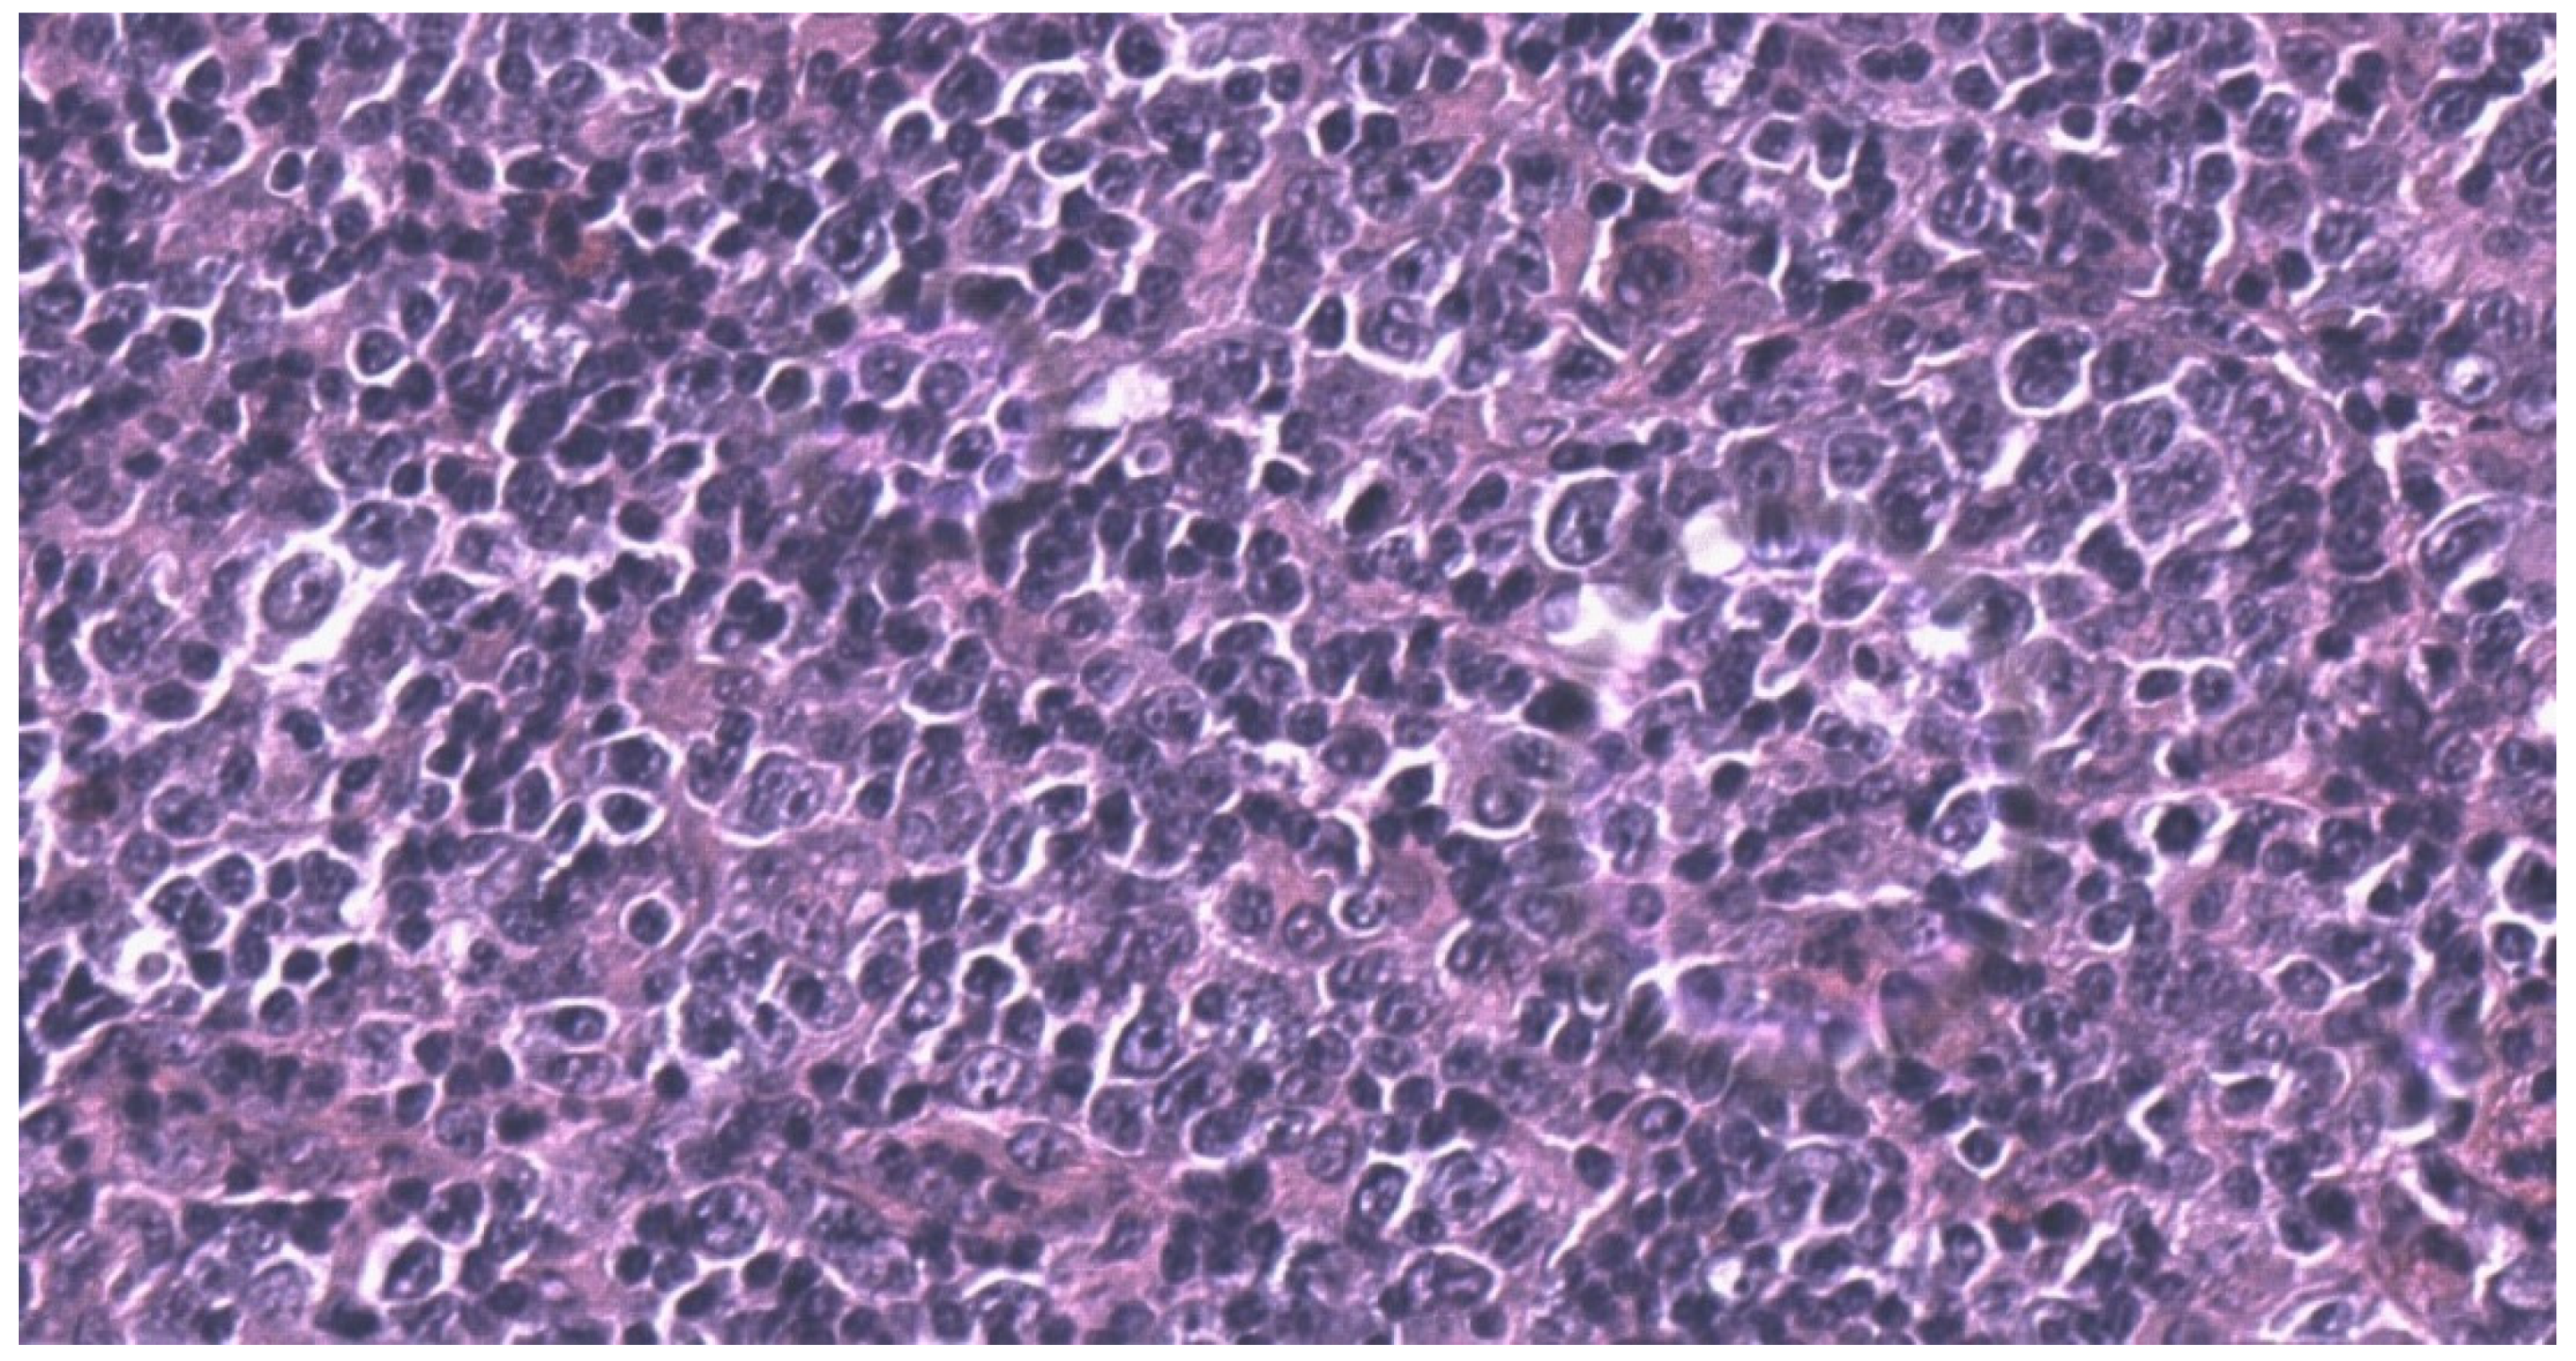

2. Case Report